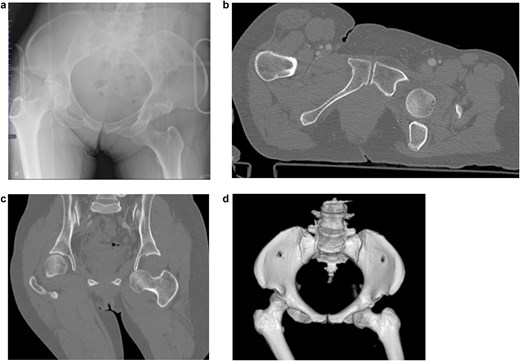

A 52-year-old woman was involved in a frontal motor vehicle collision while seated in the rear seat. At the time of impact, she was in a position of hip flexion, mild abduction, and external rotation (Fig. 1), a posture known to predispose to anterior dislocation. She presented to the emergency department with acute, severe left hip pain, and an inability to actively extend the affected limb. Plain radiographs and computed tomography (CT) scans revealed an obturator-type anterior hip dislocation without any accompanying fractures. Notably, a small depression was detected on the anterolateral articular surface of the femoral head (Fig. 2a–d). Based on the imaging and clinical findings, she was diagnosed with a traumatic obturator dislocation of the hip.

Imaging results at the time of transport. (a) Initial pelvic radiograph showing left femoral head dislocation. (b) Axial CT image showing femoral head displaced into the obturator foramen. (c) Coronal CT image showing inferior and medial displacement of the femoral head. (d) 3D reconstructed CT image showing the femoral head in the obturator foramen.